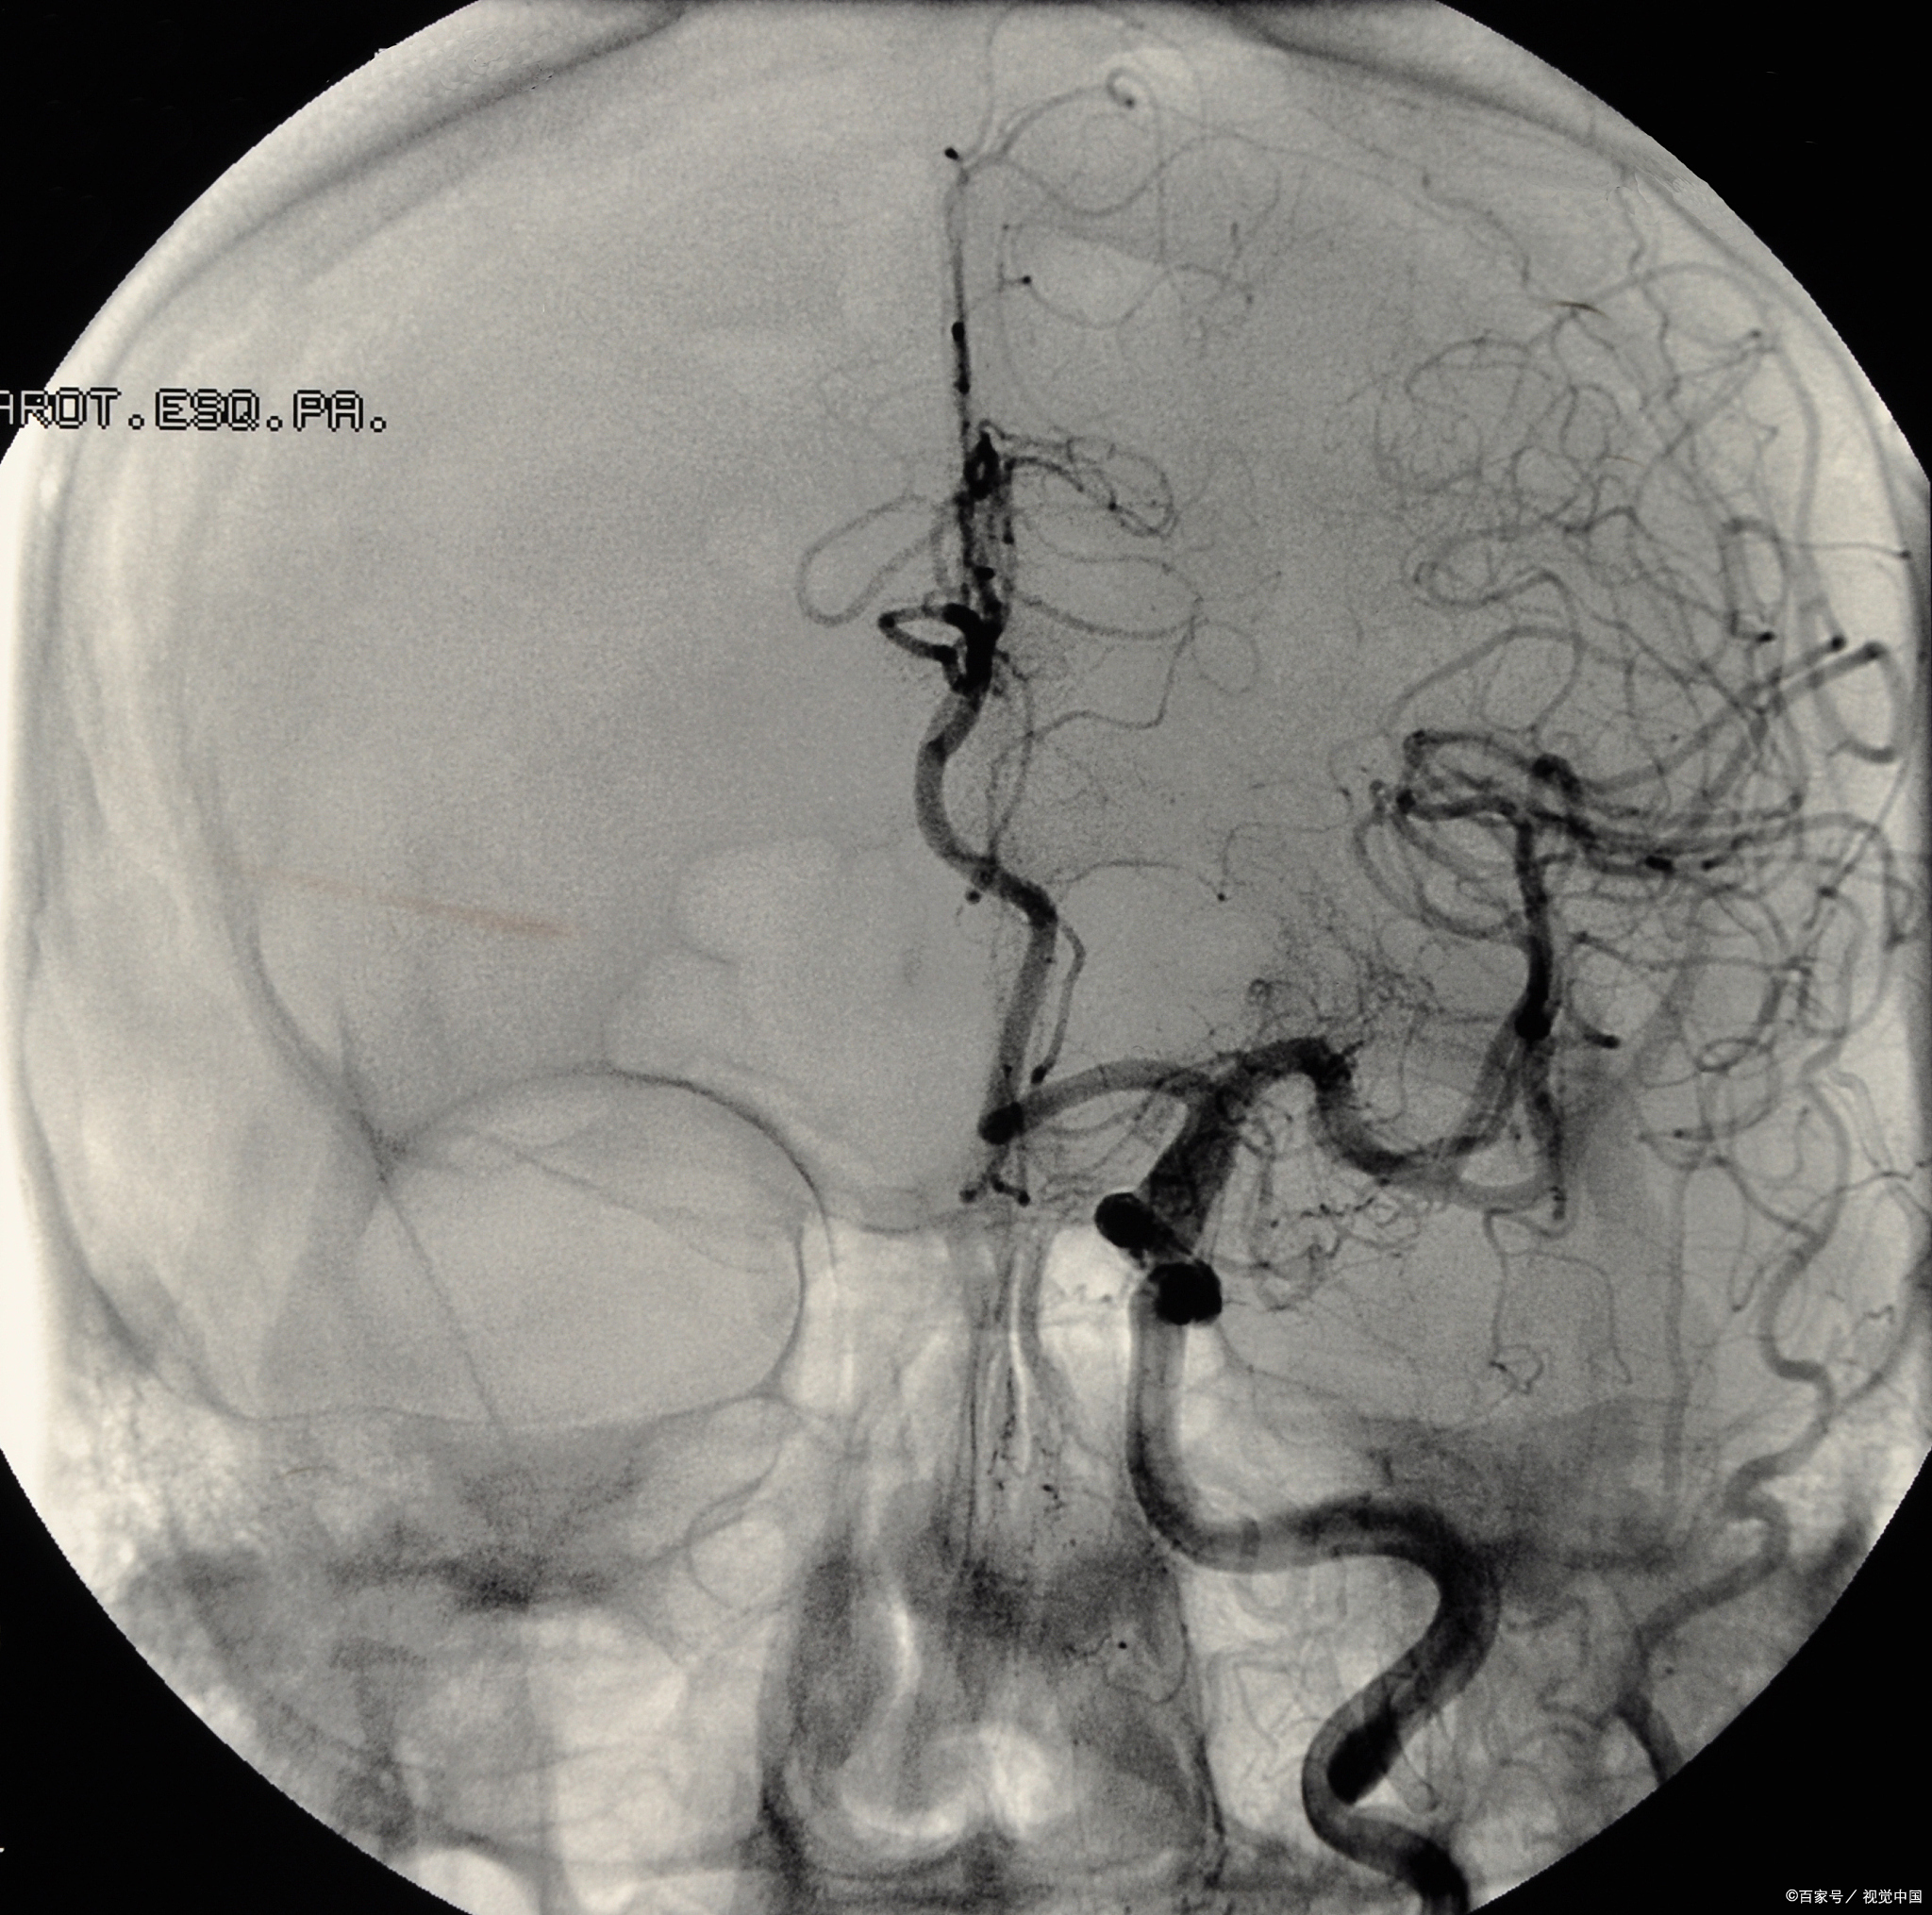

3、冠脉CTA与造影的主要区别如下检查方式冠脉CTA需要在静脉给予推注造影剂,使用高压注射器完成,然后在CT下显影冠脉造影需要在动脉进行穿刺置管,将造影导管放置到主动脉根部冠状动脉口处,进行推注造影剂,在DSA或C臂下显影显影效果与诊断准确性冠脉CTA对血管钙化有很明显的显示效果,但。

10、冠状动脉的CTA与冠状动脉的造影有很明显的区别,冠状动脉的CTA需要在静脉给予推注造影剂,然后在CT下显影,推注造影剂需要应用高压注射器来完成而冠状动脉造影是需要在动脉穿刺,如桡动脉和股动脉这两个位置,穿刺之后置管,然后将造影导管放置主动脉的根部,冠状动脉口处,进行推注造影剂,在DSA C臂下显影,然后。